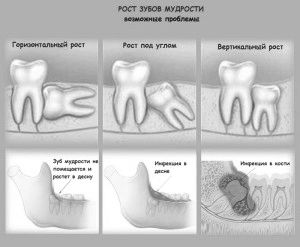

- Останній моляр росте неправильно. під кутом до решти зубах. У деяких випадках він взагалі розташований горизонтально, і в процесі росту впирається або в щоку, або в корені сусіднього зуба. Такий зуб однозначно слід видаляти ще до прорізування хірургічним шляхом.